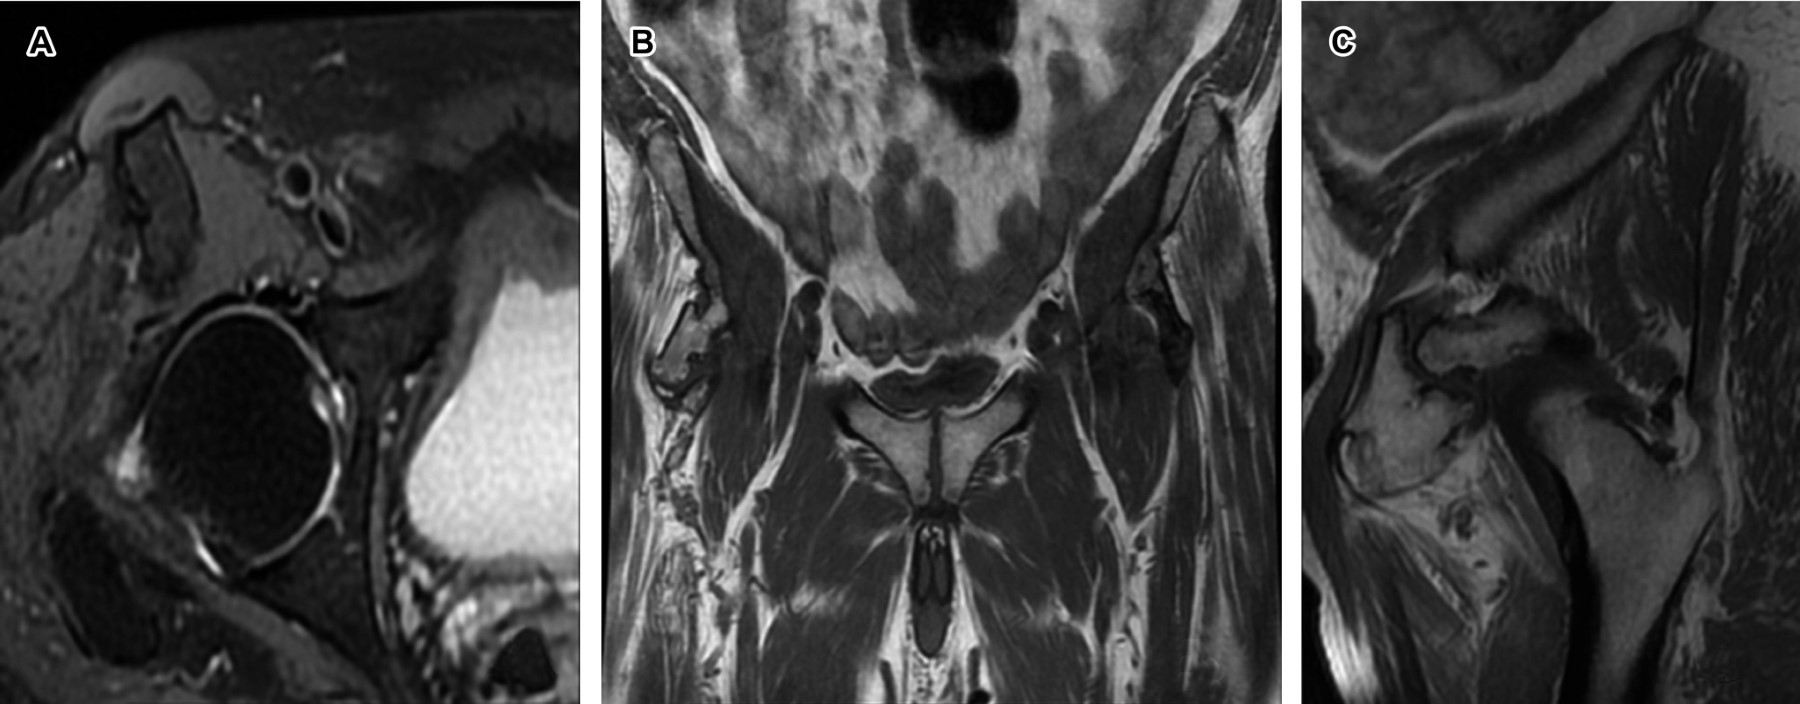

A 74-year-old male patient whose diagnostic impression was a discrete increase in synovial fluid in the right coxofemoral joint compared to the left side. The findings in the right hip suggested the possibility of bony prominences, considering the articulated right pelvic finger.

Figure 2